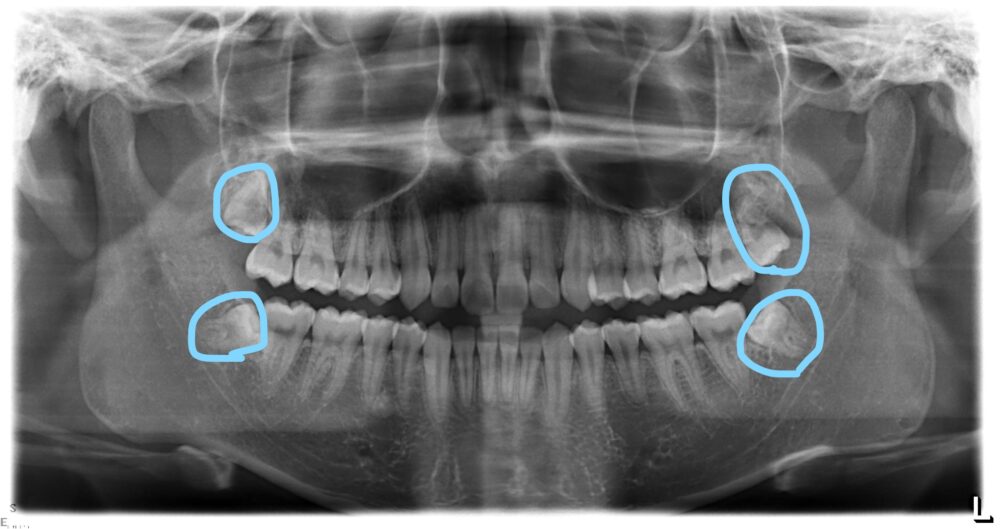

青丸のとこ4本が親知らずです・・・・横から生えている3本・・・どうみても放置していたら悪さする感じしますよね・・